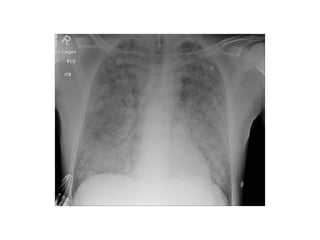

2-Classification :

-May be classified on a chest radiograph into 5

stages :

Stage 0 : normal chest radiograph

Stage I : hilar or mediastinal nodal enlargement

only

Stage II : nodal enlargement and parenchymal

disease

Stage III : parenchymal disease only

Stage IV : end-stage lung (pulmonary fibrosis)

Stage I